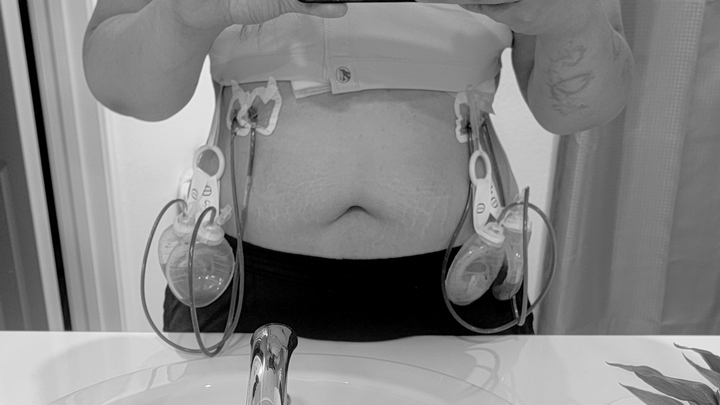

In April, my wife found a lump in my right breast. I quickly dismissed it. I thought it had to be nothing, I was only 38. She made me make an appointment anyways. After 2 mammograms, an ultrasound and a biopsy, I got a call. By the end of May they confirmed it was breast cancer. When I got the news, all I could think, was damn...thats a bummer, It blindsided me because i really made myself believe it was nothing. And then I realized I'd have to tell my wife and my mom, and everyone. Cancer wasn't going to just change my life, but it would the lives of everyone who loved me. After more tests and doctors visits and making really hard surgical decisions, I finally had a surgery date, August 19th. Thats the day cancer took both of my breasts. Double mastectomy, lost 4 lymph nodes and preparation of reconstruction. But I'm here, the first part is done. Its very painful, as one could imagine. Not just physically painful but also mentally painful. I didn't ask for cancer, but it came anyways. I didn't want to have a full mastectomy but it was necessary. I didn't want my body dissected but it saved my life. So its a little hard to look in the mirror right now, but I'll get there. This journey will be a little long and painful. I wont be at work for some time. So my family wanted to start this gofundme page to help me while I focus on my health. My family and I ask if you could please share this page for donations and share my story. And please encourage yourselves and your loved ones to see the doctor and stay on top of your health because life is too beautiful to miss.